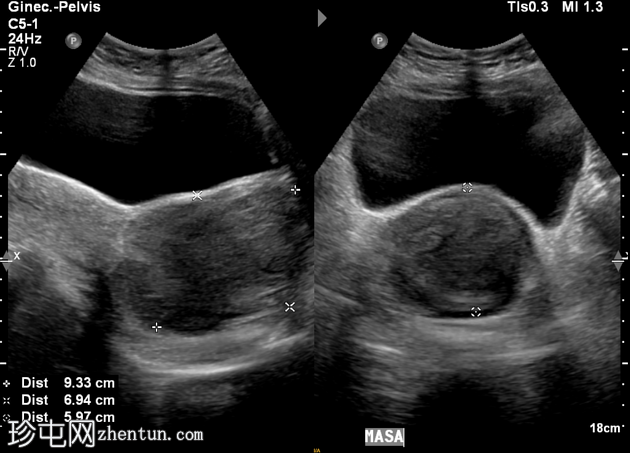

1.png

横切面

子宫前倾位。纵径、前后径、横径分别为145 × 41 × 58 mm。

由于存在一个边界清晰、形态不规则的低回声实性肿块,子宫呈异质性回声。该肿块位于宫颈区域,似乎延伸至阴道方向,大小为93 × 69 × 59 mm。

超声检查发现宫颈区域有一实性异质性肿块,延伸至阴道。鉴别诊断包括宫颈平滑肌瘤和宫颈肿瘤。需行盆腔MRI检查以明确病变性质。